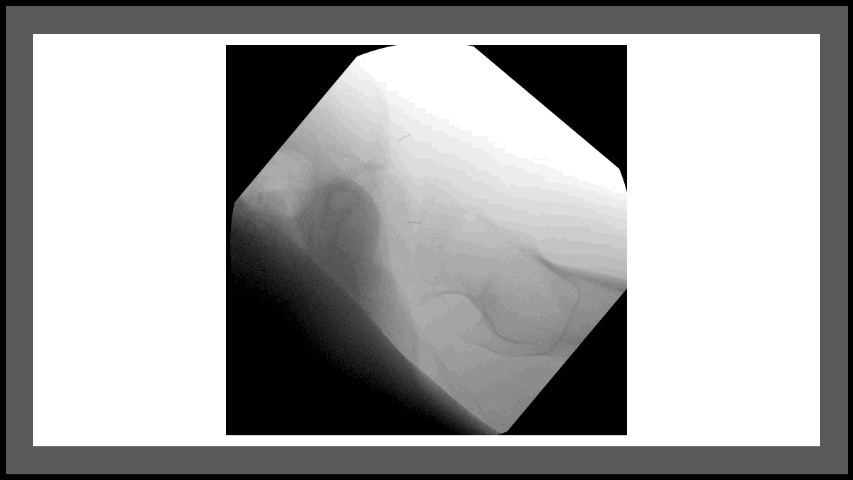

![]() Unstable pelvic ring and sacral fractures | ![]() Lisfranc midfoot fracture-dislocation | ![]() Femoral head fracture | ![]() Ankle fracture dislocation |